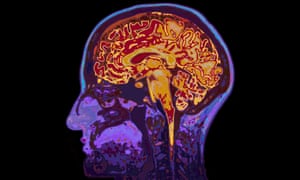

‘The brain is the body. Mental health is physical health.’ Photograph: Alamy

The problem we have with talking about mental health is that we still don’t think of it as an equal priority with physical health. This is wrong not simply because it leads to less money being spent on mental health service provision by governments, but also because it fails to see that the whole idea of mental health shouldn’t be an isolated one.